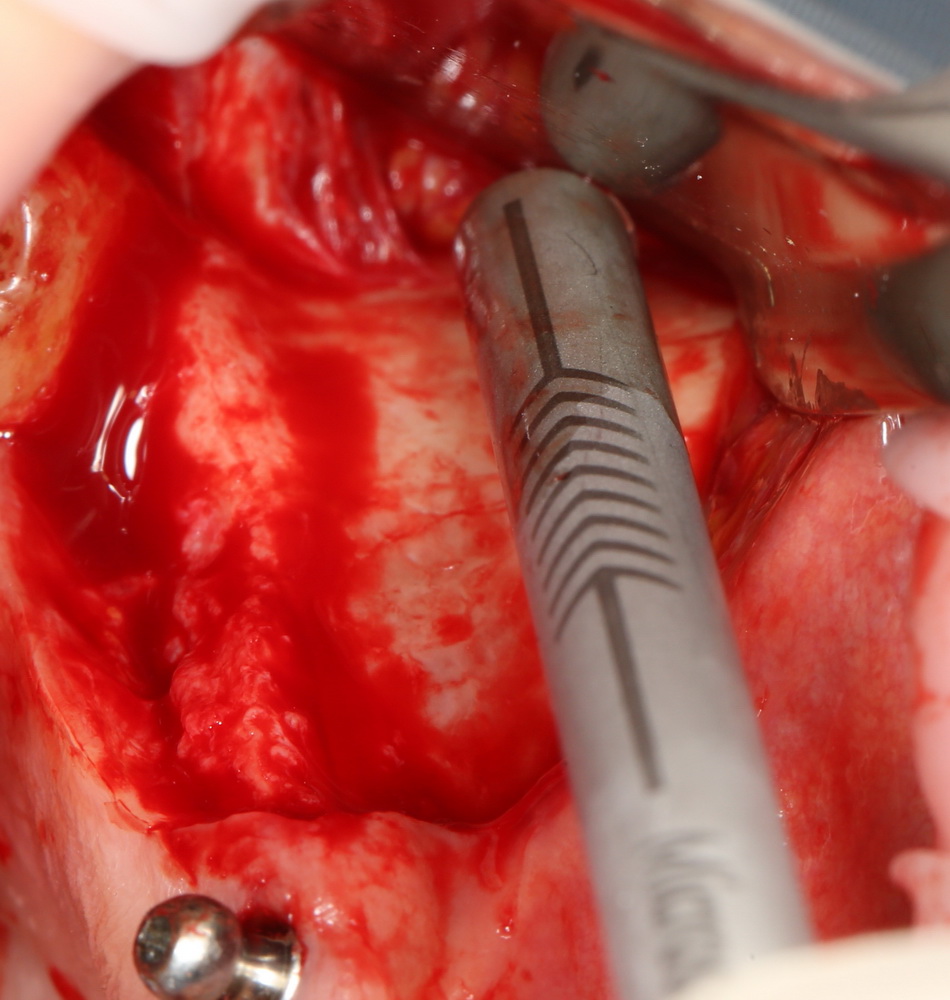

с трудом выковыриваем сетку и ищем имплантат:

чтобы поставить формирователь: